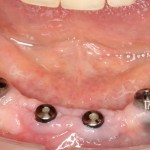

Можно приступать к формированию десны. Напомню, что для длительного и счастливого функционирования имплантов в боковом участке необходима кератинизированная десна в объеме не менее 2 мм вокруг шейки импланта. Где ее взять? Все там же, с небного края альвеолярного гребня!

Следующая задача — найти импланты, которые полностью заросли костной тканью:

Ставим на них формирователи десны, ушиваем рану с расчетом на вторичное натяжение.

Через пару недель область, где мы провели уже две операции, выглядит примерно так:

или, если снять формирователи: